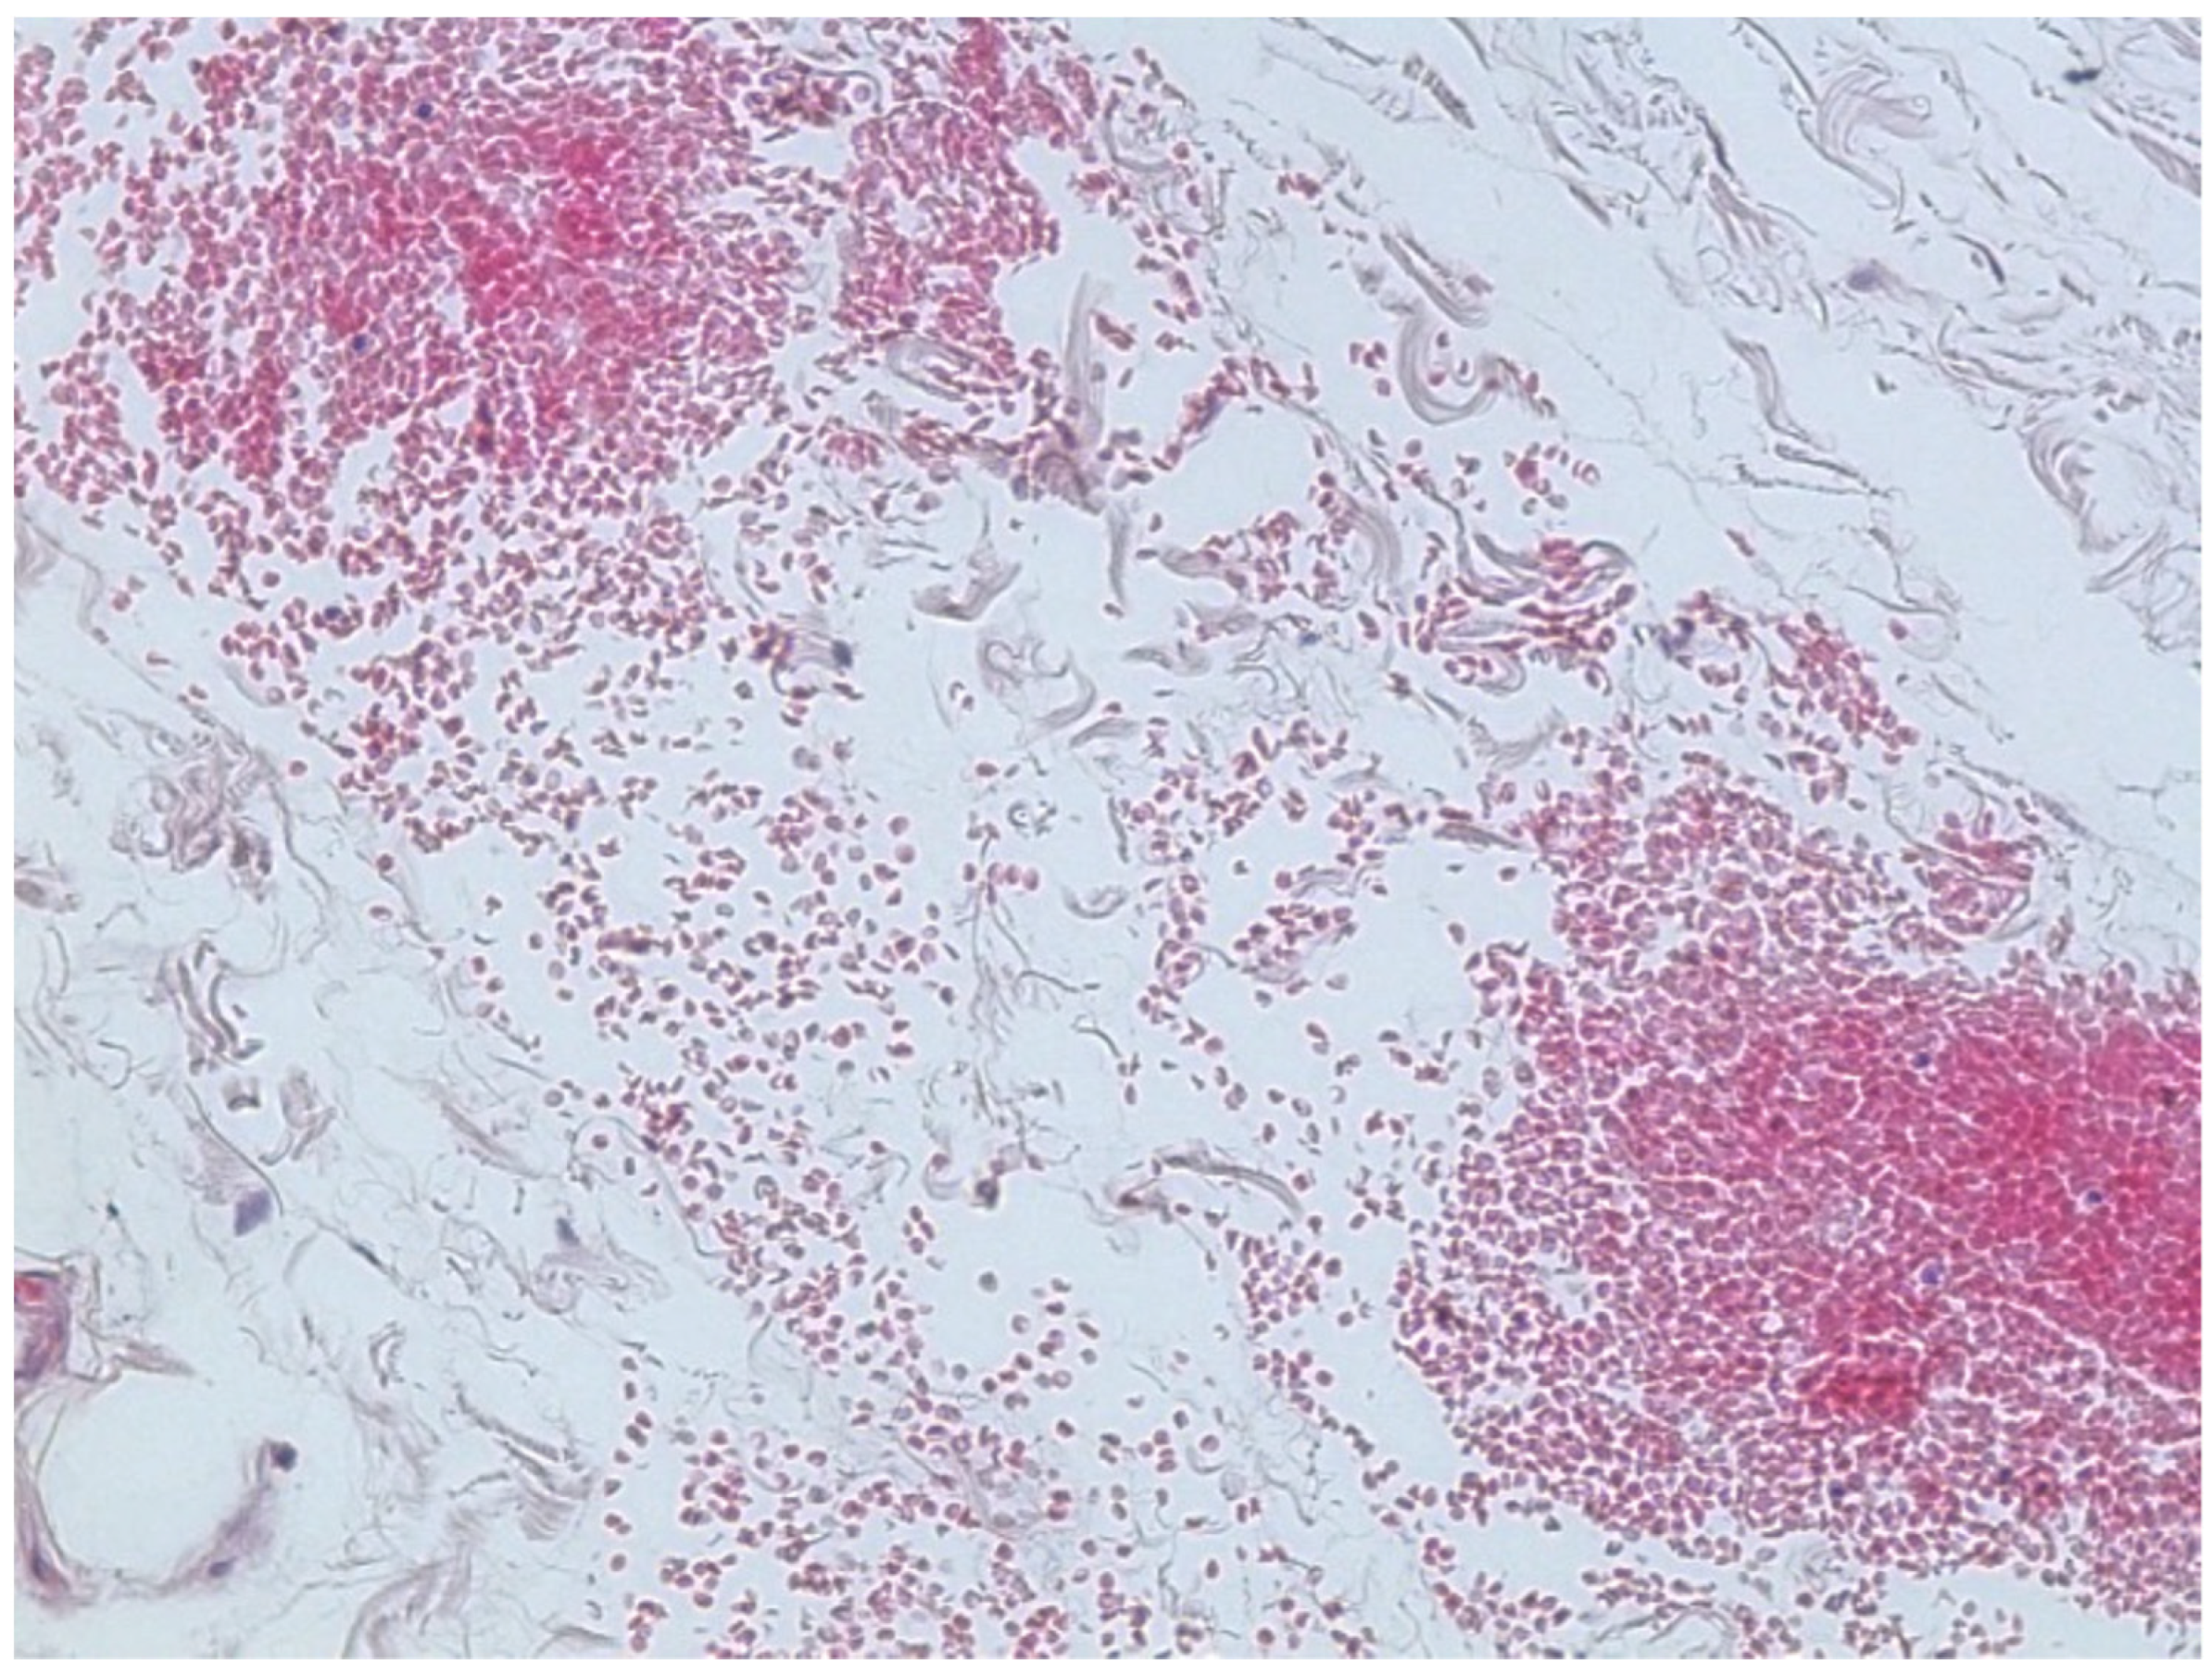

Microscopic observation of tissue sections stained with hematoxylin and eosin showed marked pulmonary congestion (Figure 7), micro- and macrovesicular hepatic steatosis (Figure 8), as well as vacuolization of the basal cells of renal tubules (Figure 9). Gastric wall showed edema and vascular congestion involving mucosa and submucosal layers and focal erosions of the mucosal surface consisting of necrotic foci delimitated by a dense lympho-histiocytic infiltrate (Figure 10). At the level of the skin discoloration (Figure 11), small hemorrhagic extravasations in the dermis were detected.

Figure 11. Skin with small hemorrhagic extravasations in the dermis.

The thermic lesions from cold (frosts) consisted in multiple and diffused areas of cutaneous reddish discoloration, localized on the face (right auricle, left malar region), upper limbs (dorsal surface of the forearm and hand bilaterally), and lower limbs (anterior surface of the knee and leg bilaterally, dorsal surface of the foot bilaterally, plantar surface of the left foot). These lesions were related to the low temperature conditions at which the victim was exposed, due to the occurrence of reactive vasomotor phenomena of transient vasoconstriction and passive hyperemia from vasal paralysis. Histological analysis showed small hemorrhagic extravasations, attributing these lesions to a second degree.